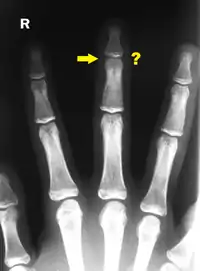

- (anatomy) A slender jointed extremity of the human hand, (often) exclusive of the thumb.